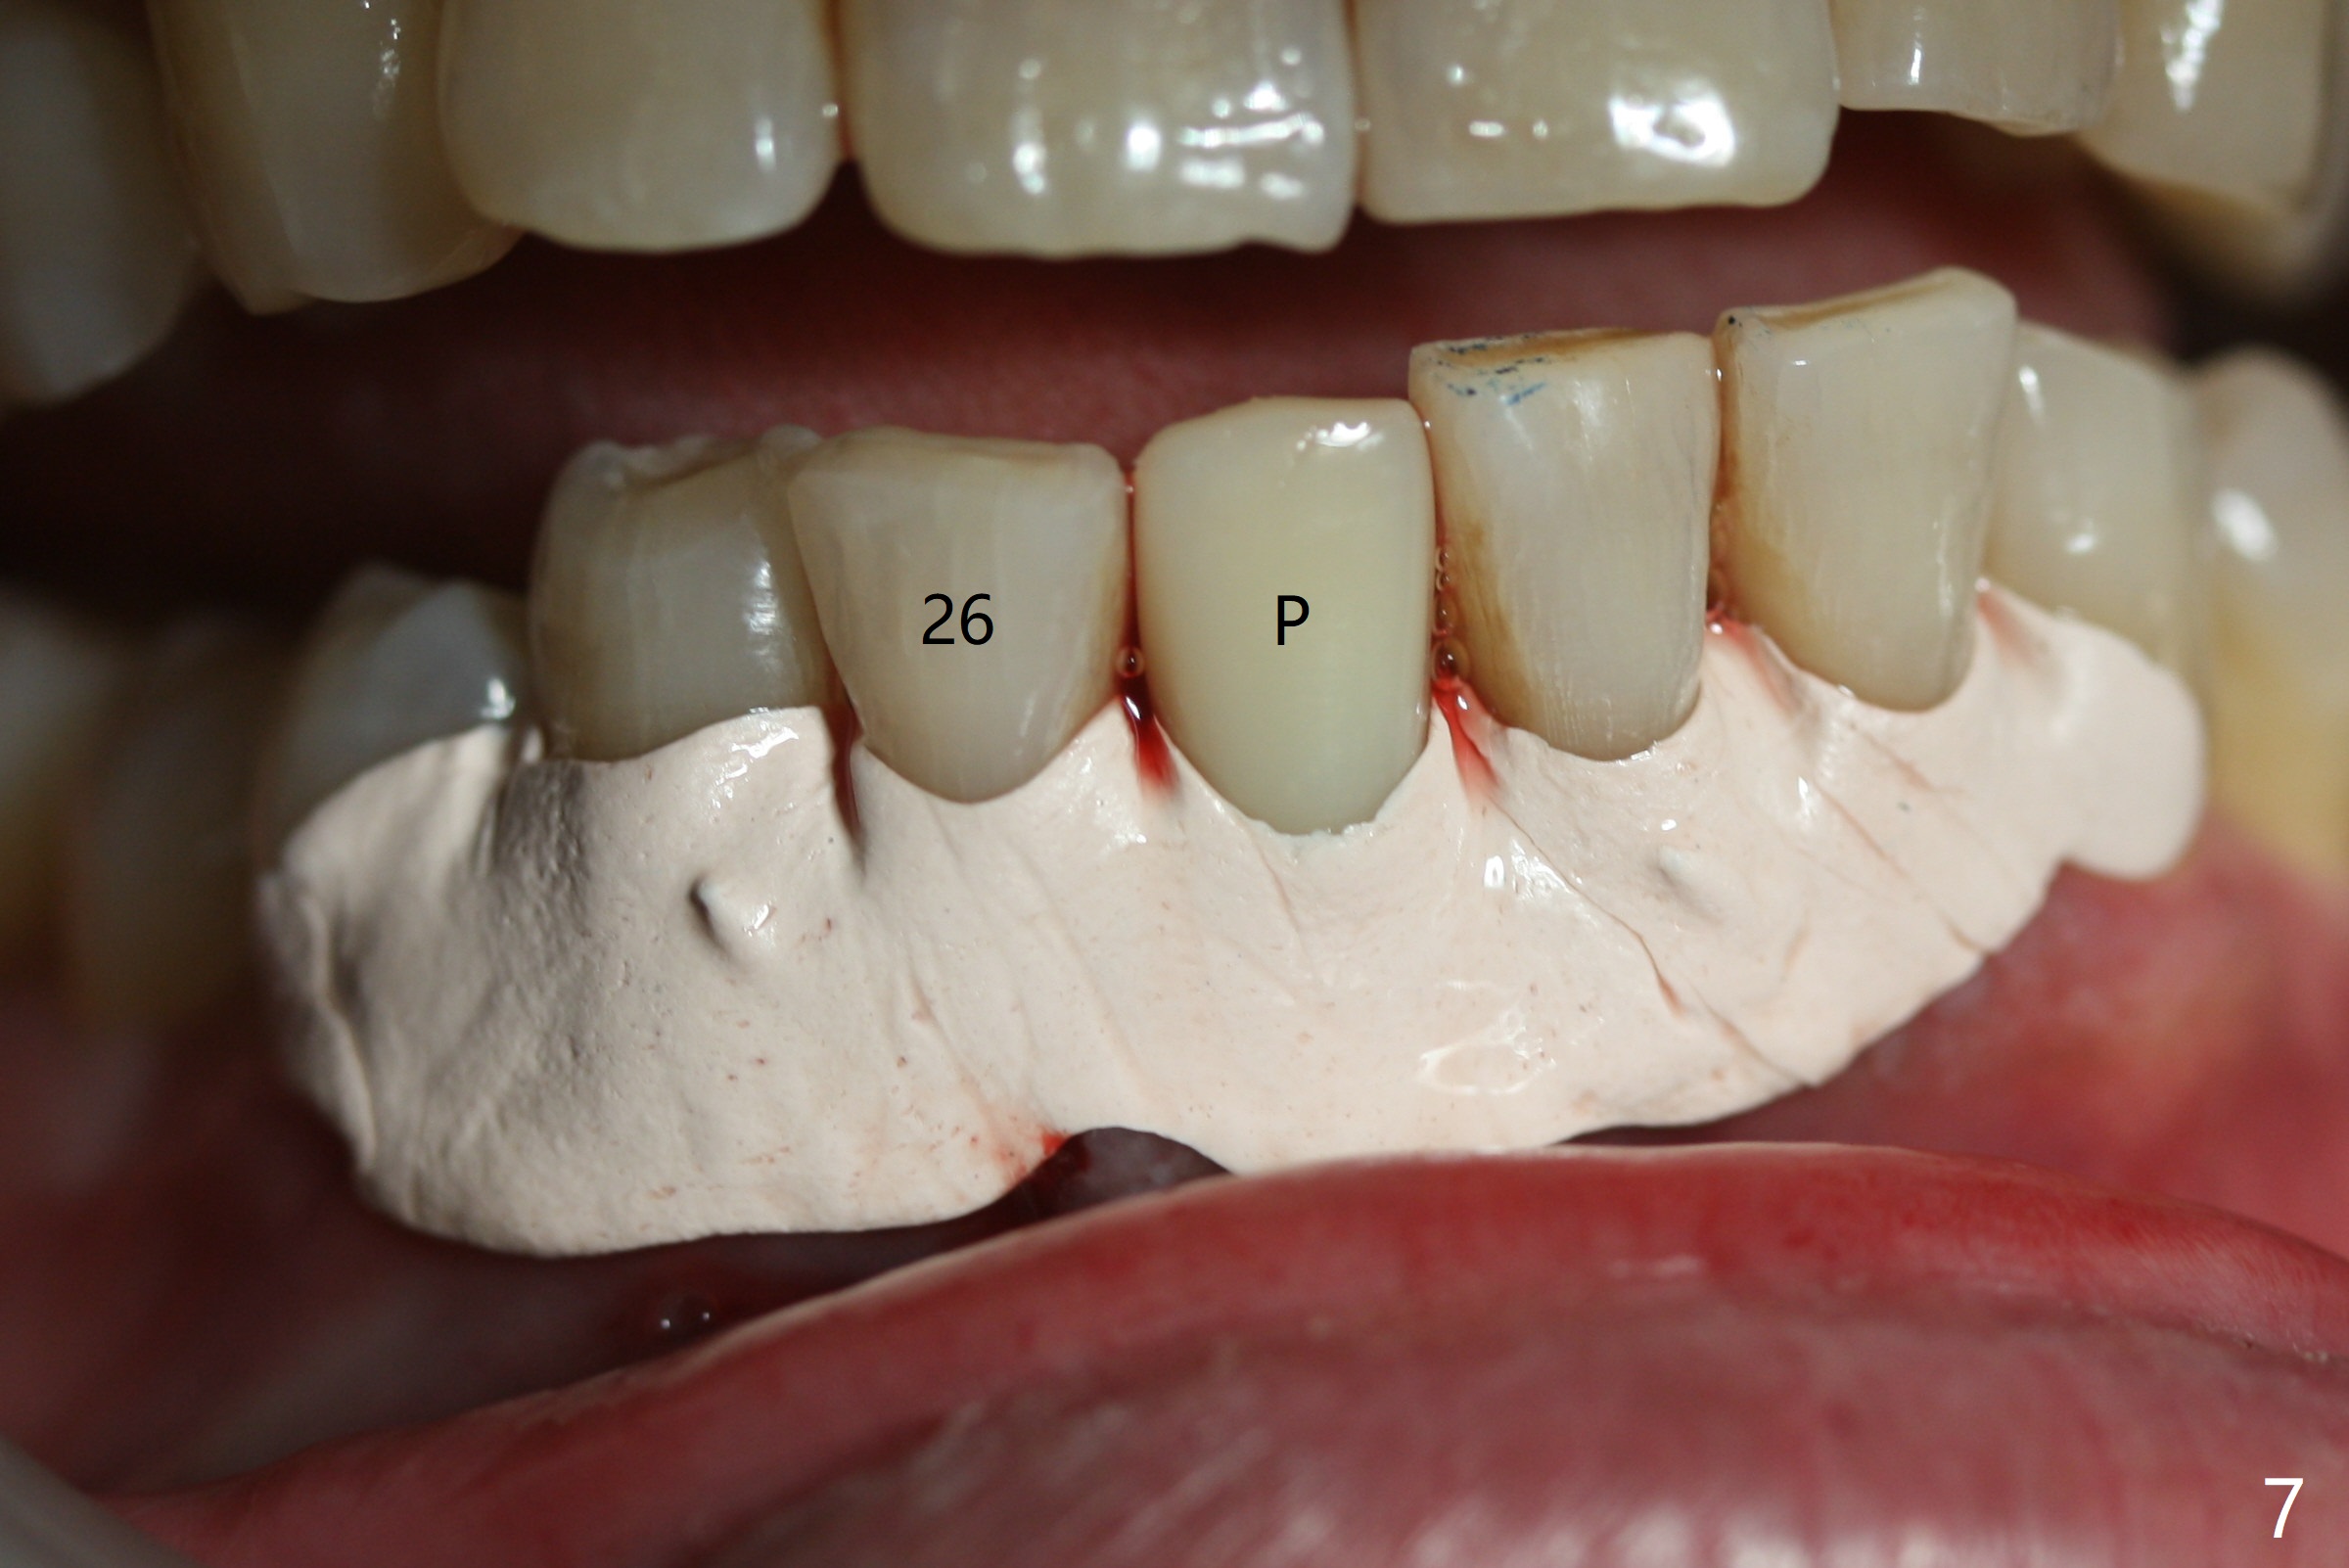

Implant

Out of financial concern, the patient does not agree to have the tooth #26 extracted. Due to atrophy of the most coronal ridge buccally at #25 (Fig.1,2 *), osteotomy is initiated difficult and distal (Fig.3). After 1.2 mm drill removal (Fig.3' black area), Lindamann bur is used to move the osteotomy mesial (red area). A 2x12(4) mm 1-piece implant is placed (Fig.4,5); the buccal defect is packed with allograft (Vanilla, .5-1 mm cancellous/cortical mixture, *). When the tooth #26 fails, a 2 mm implant will be placed (Fig.6 blue). Following abutment adjustment, a provisional is fabricated (Fig.7 P); note the lower incisal edges of #25 and 26, as compared to those of the neighboring teeth. To reduce occlusal trauma, the incisal edge of the tooth #26 has been decreased (Fig.5 open arrow). The implant threads seem not to be exposed 4 months postop (Fig.8), although the tooth #26 has mobility II.